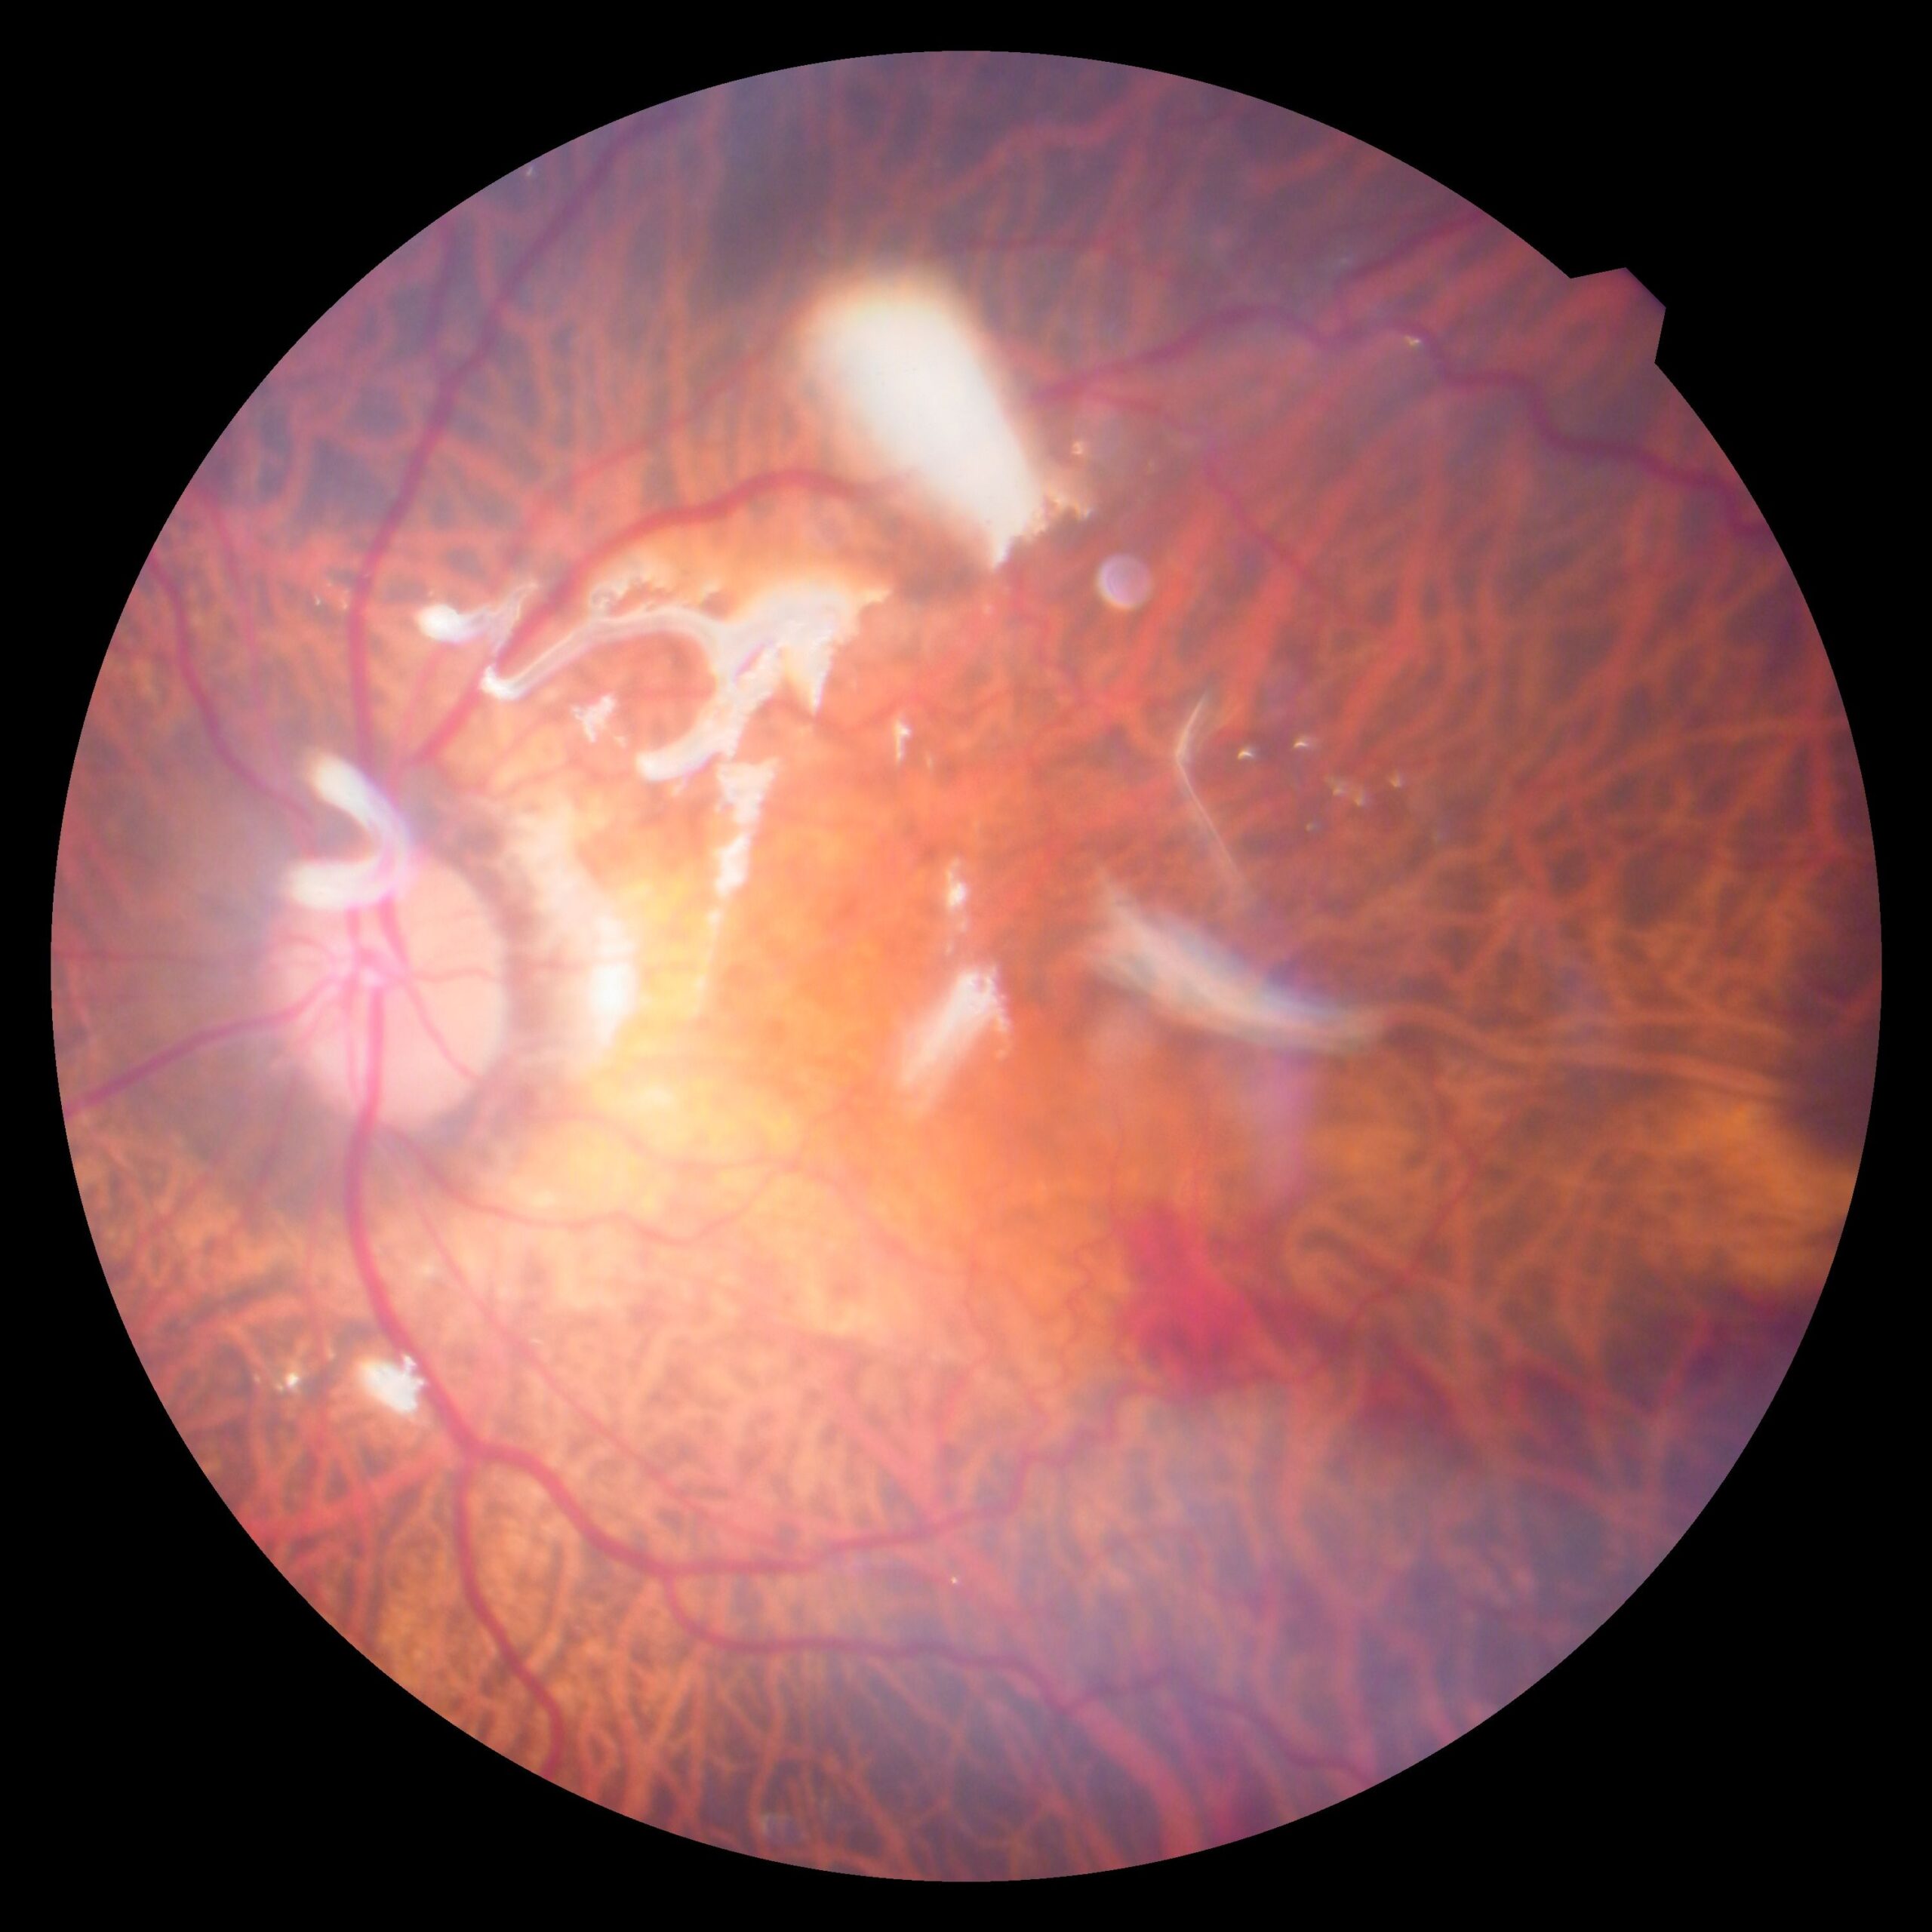

Diabetic Retinopathy, Retinal Detachment, Macular Hole, ERM, Vitreous Hemorrhage.

A minimally invasive surgery to treat retinal diseases by removing the vitreous gel.